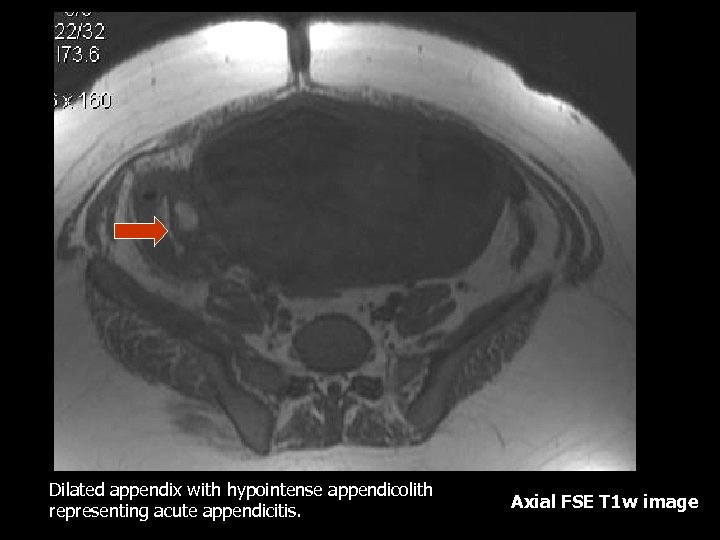

Dilated appendix with hypointense appendicolith representing acute appendicitis. Axial FSE T 1 w image

Appendicitis • Most common non-obstetric surgical condition, also the most delayed due to overlap of symptoms with normal pregnancy(3). • Most reliable symptom is right lower quadrant pain(3). • Leukocytosis may be physiologic since the normal range in a gravid patient may range from 6, 000 to 16, 000(3). • Delay may cause increased fetal and maternal mortality therefore early diagnosis is essential(3).

Appendicitis MRI Findings: • Marked wall enhancement and distention with fatsuppressed, contrast-enhanced T 1 weighted images (2). • However it is possible to make the diagnosis without contrast (2). • T 2 weighted images with fat suppression can show a thickened appendiceal wall, intraluminal fluid and peri -appendiceal inflammation. • Appendicolith will appear as a round signal void in all sequences, however it might be difficult to differentiate from intra-luminal air.